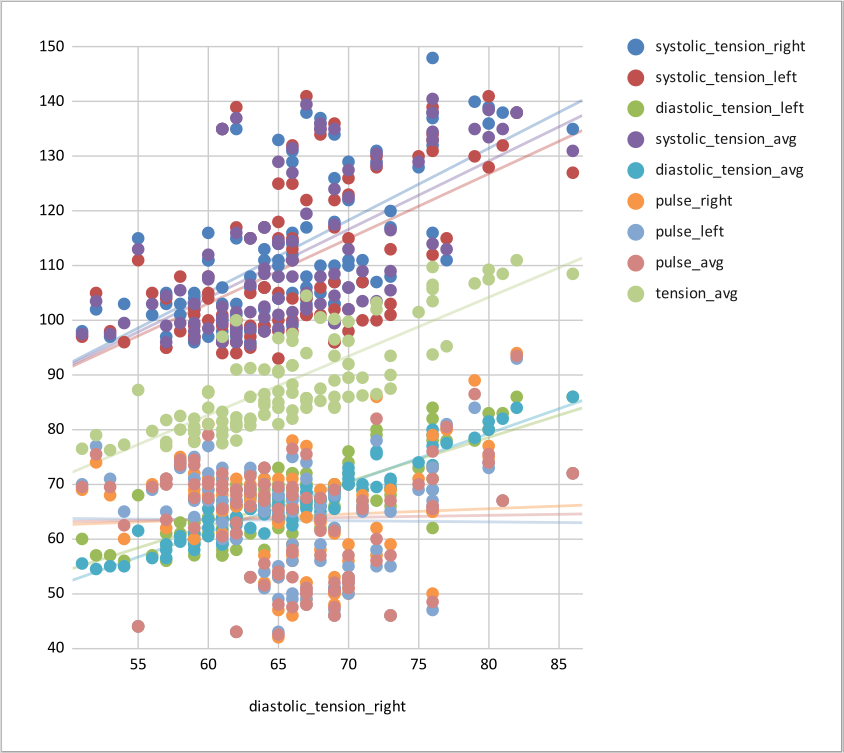

CVR and blood pressure

Due to its nature as homeostatic and cerebrovascular process, CVR is modulated by systemic changes in blood pressure¹

1. Fierstra et al. 2013 (J. Physiol.); 2. e.g. Hetzel et al. 1999 (Stroke)

Previous studies with Transcranial Doppler Ultrasound suggest to take into account blood pressure when measuring CVR²

To our knowledge, the impact of blood pressure on BOLD-fMRI based CVR estimation has not been assessed yet

Vital signs (VS), measured before the MRI session, while the subject was lying supine on a bed, once on the left arm and once on the right arm:

- Cardiac pulse

- Blood pressure (systolic and diastolic)

We averaged the two measurements and computed the Mean Arterial Pressure (MAP) and the Pulse Pressure (PP):

Correlation between VSs

Correlation between VSs

Results: blood pressure

Results: blood pressure

Results: blood pressure

Both MAP and PP should be taken into account in CVR experiments, especially in comparisons between subjects or between regions!

- Stationary blood pressure changes, expressed as MAP and PP, as well as sex, impact regional CVR estimation differently across sessions and subjects

Dynamic blood pressure changes are expected to impact CVR estimation, hence continuous blood pressure recordings are required to assess the matter